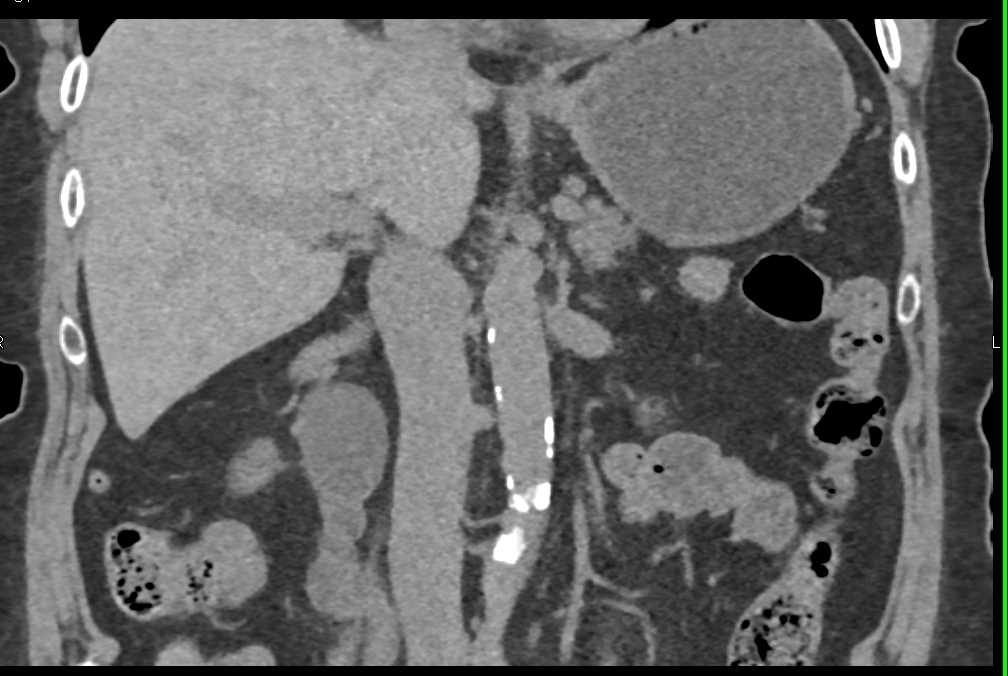

Large Necrotic Nodal Mass Obstructs Ureter